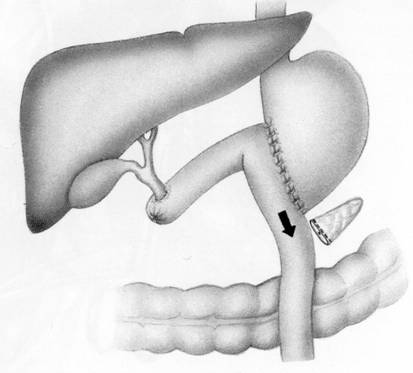

n ВНУТРЕННЕЕ ДРЕНИРОВАНИЕ ВНЕПЕЧЕНОЧНЫХ ЖЕЛЧНЫХ ПРОТОКОВ:

n БИЛИОДИГЕСТИВНЫЕ АНАСТОМОЗЫ

n ПАПИЛЛОСФИНКТЕРОТОМИЯ

n ВТОРИЧНЫЙ ПАНКРЕАТИТ

ПРИ 3AБОЛЕВАНИЯХ ЖКТ:

n ЯЗВЕННАЯ БОЛЕЗНЬ - РЕЗЕКЦИЯ ЖЕЛУДКА, ВАГОТОМИЯ В РАЗЛИЧНЫХ МОДИФИКАЦИЯХ,

n ДУОДЕНОСТАЗ – ДУОДЕНОЕЮНОСТОМИЯ, ОПЕРАЦИЯ СТРОНГА (НИЗВЕДЕНИЕ ДВЕНАДЦАТИПЕРСТНО-ТОНКОКИШЕЧНОГО ИЗГИБА)